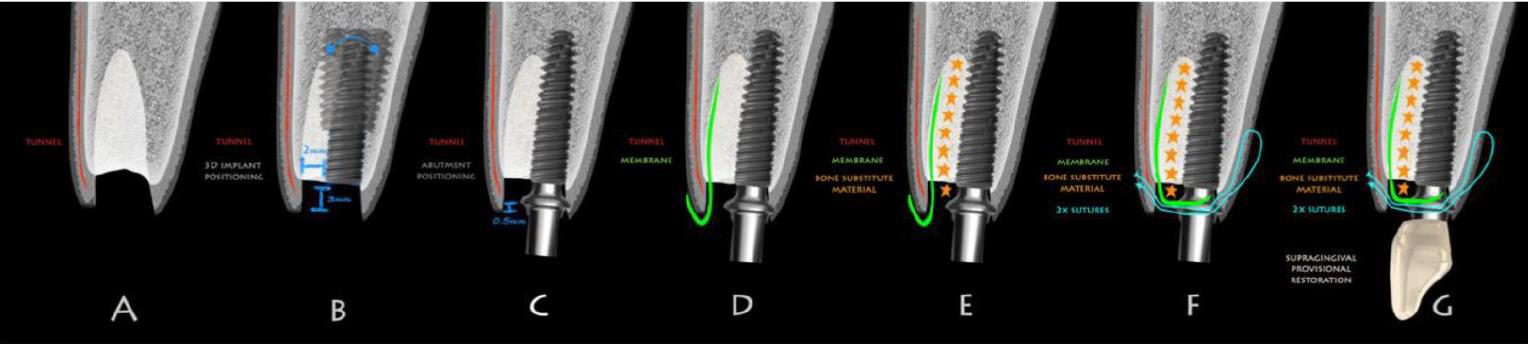

植牙的時機與步驟

Type 1、2需要額外的技巧,因為傷口仍在癒合初期;Type 3、4比較保守,但齒槽嵴已經偏離原先的位置了,在判斷植體的apical-coronal深度時比較困難,最好的參考點是鄰牙CEJ或是未來要做假牙的牙冠邊緣往下3mm,短於2mm會有美觀風險,植體的平台或是金屬部分可能會露出來。

Type I

- 即拔即種

- 保留原本的骨頭

Type II

- 4-8w

- 唇側沒有骨頭

- 先讓軟組織長夠多再來GBR植牙

- 用膠原蛋白

- 軟組織總量夠多就不須做tension release